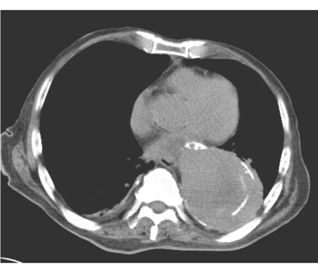

患者,男,45岁。突感胸骨后疼痛来院就诊。胸部CT平扫图像如下图:

1.本例应诊断为

A.胸主动脉瘤

B.主动脉壁内血肿

C.胸主动脉夹层

D.胸主动脉破裂

E.主动脉炎

2.若要明确诊断可建议进一步做何检查

A.X线平片

B.胸部超声

C.MSCTA

D.MRI

E.放射性核素扫描

正确答案:1.C;2.C